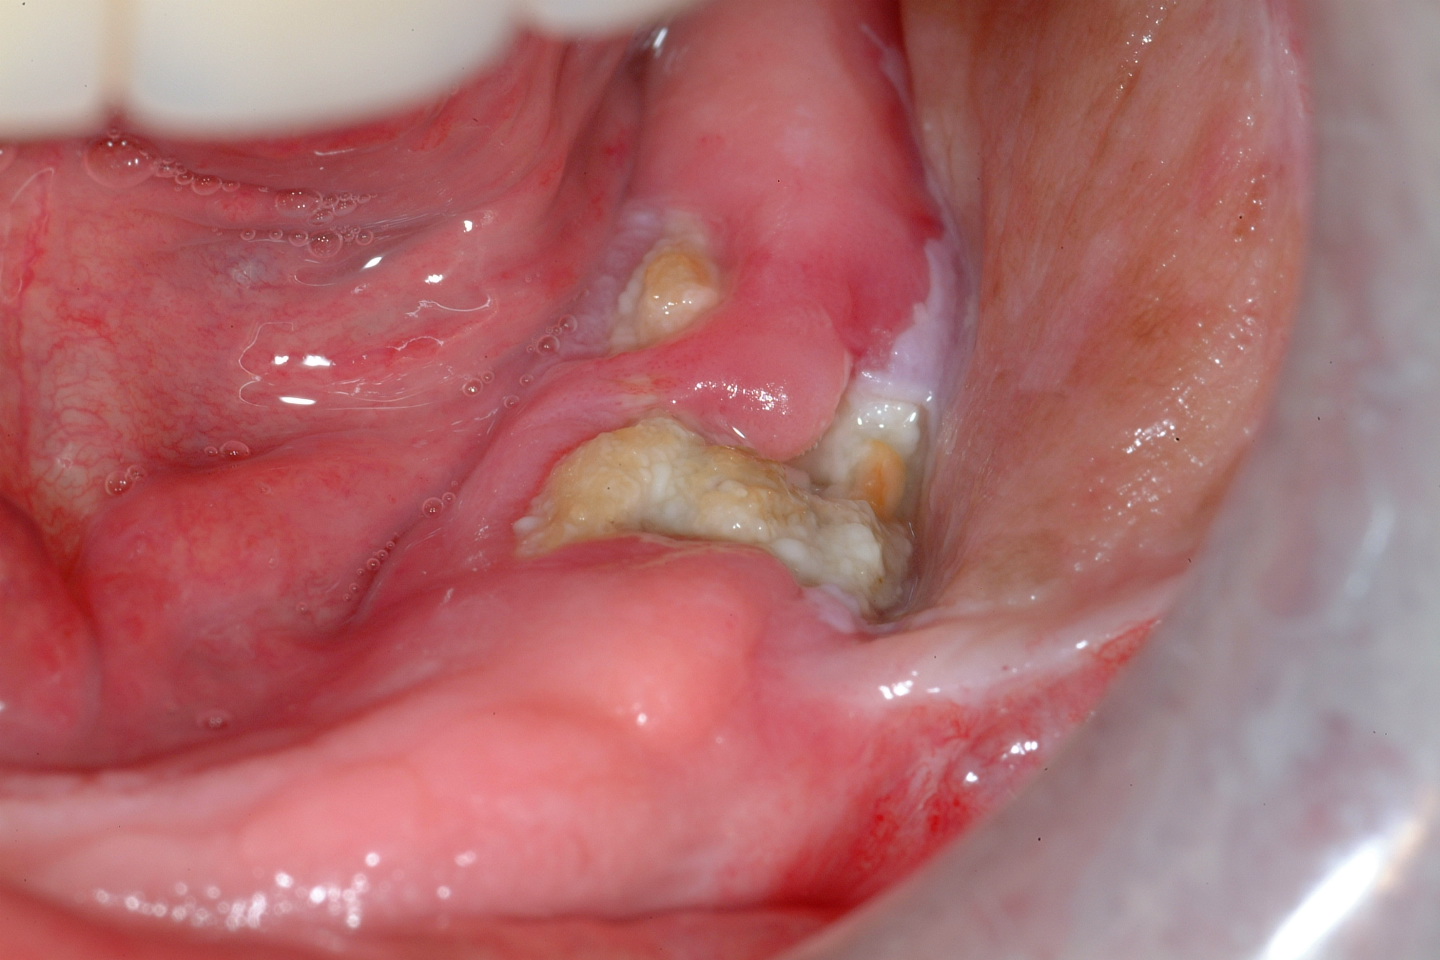

Figure 1, Figure 2 and Figure 3 show examples of different ORN conditions.

Figure 4 and Figure 5 show examples of MRONJ of the maxilla and mandible, respectively.